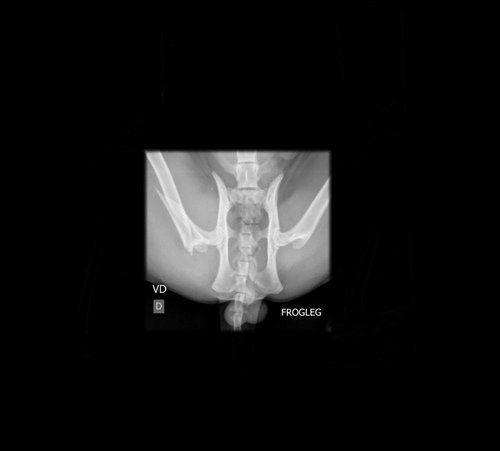

Meu nome é Jen, e sou tutora do pequeno Frederico, um gatinho muito querido de apenas 10 meses que está passando por um momento difícil. Recentemente, ele sofreu um acidente no dia (11/01) e fraturou o fêmur, uma lesão que o impede de se movimentar e está causando muita dor.

O Frederico precisa urgentemente de uma cirurgia para corrigir a fratura e recuperar a sua qualidade de vida. O custo do procedimento, internação e placas para a cirurgia é de R$ 4.000,00, um valor que infelizmente não consigo arcar sozinha. Por isso, venho pedir a ajuda de quem puder contribuir com qualquer valor.